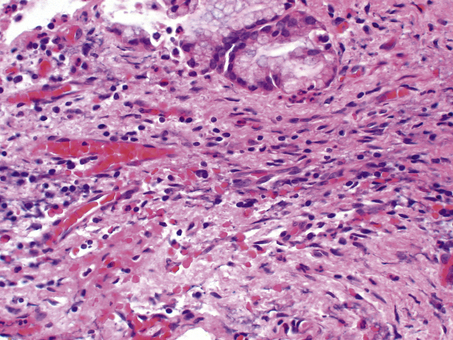

During organisation, new capillaries grow into the inert material (inflammatory exudate), macrophages migrate into the zone and fibroblasts proliferate under the influence of TGF-beta, resulting in fibrosis and, possibly, scar formation. A good example of this is seen in the pleural space following acute lobar pneumonia. Resolution usually occurs in the lung parenchyma, but very extensive fibrinous exudate fills the pleural cavity (Fig. 10.11). The fibrin is not easily removed and consequently capillaries grow into the fibrin, accompanied by macrophages and fibroblasts (the exudate becomes ‘organised’). Eventually, fibrous adhesion occurs between the parietal and visceral pleura (Fig. 10.13). Fibrous adhesions also occur commonly in the peritoneal cavity after surgery or an episode of peritonitis; these can hamper further surgery and can also lead to intestinal obstruction.

image

Fig. 10.13 Organisation of the fibrinous pleural exudate. Capillary loops are growing into the exudate, accompanied by fibroblasts and capillaries.